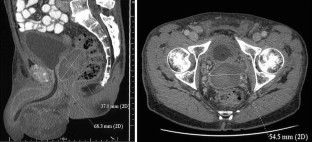

Fig. 1